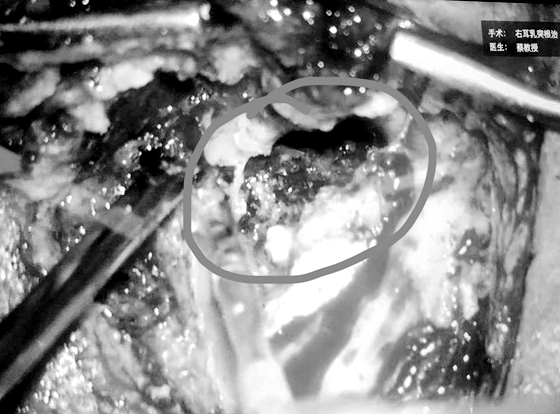

近日,湘雅常德医院耳鼻咽喉头颈外科成功为1名中耳胆脂瘤患者行经外耳道耳内镜下人工听骨植入术。经过耳鼻喉科专家团队近2小时的精细操作,在为患者彻底清除胆脂瘤病变的基础上,为该...